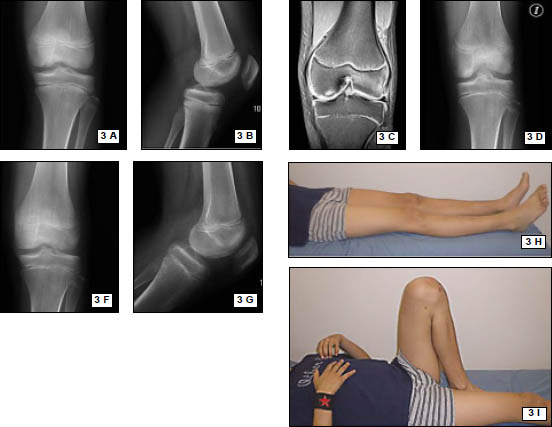

Se realiza un mini abordaje anterior de rodilla 2 cm proximal al polo inferior de la rótula y 3 cm distal al mismo, luego se realiza la esqueletización del polo patelar distal cruentándolo a la demanda. Mediante dicho gesto se reconoce la superficie ósea permitiendo la implantación precisa de los arpones, centralizándolos en plena masa esquelética, se colocan en forma paralela 2 anclajes óseos de 3.5 mm (Arthrex). (Fig. 3 y 4)

Figura 3: Visión intraoperatoria de la lesión del tendón patelar, colocación de 2 arpones paralelos

Figura 6: Rx Frente Postoperatorio, correcta posición de anclajes óseos.

Figura 7: Rx perfil Postoperatorio, correcta posición de anclajes óseos, correcta altura patelar.

Se realizaron radiografías de control en el postoperatorio inmediato. (Figs. 6, 7)

El protocolo postquirúrgico de la rodilla comprendió la inmovilización en extensión con una férula ballenada durante 3 semanas, autorizando activamente sólo ejercicios isométricos. Luego de esa etapa inicial, se permitió el incremento progresivo del rango de flexión asistido pasivamente: 0°- 45° hasta la cuarta semana, 0°-90° en la quinta semana. En la sexta semana se comienza con la movilidad activa asistida y libertad completa para la fle- xión. (Figs. 8, 9, 10)

Figura 8: Abordaje anterior reducido 2° mes postopera- torio.

Figura 9: Extensión activa 2° mes postop

Figura 10: Flexión completa, 2° mes postop.